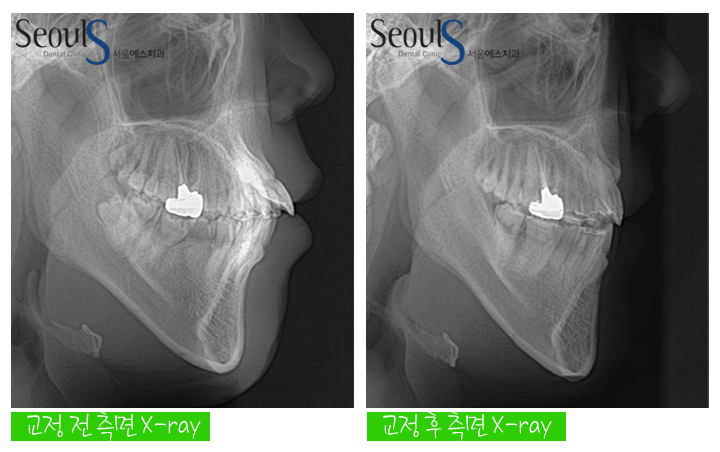

교정 전후 측면 X-ray 모습입니다

앞으로 돌출된 치아가 교정 후 개선 된 모습이죠